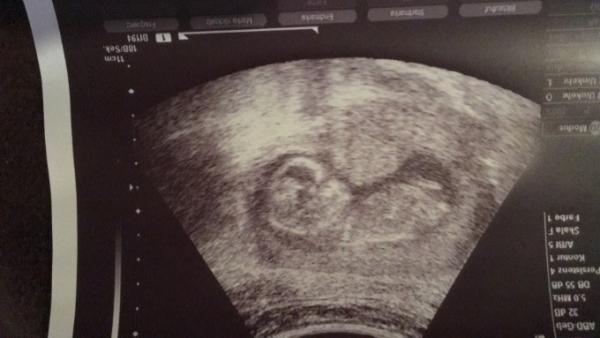

Hi ;) Ja, alles absolut unauffällig! Bei dir hoffentlich auch? Heute gab es dann auch bei meiner Gyn den Zettel vom ETS mit den genauen Zahlen... Und es gab auch ein neues Bild...Leider hat uns das kleine den Rücken zugedreht... Evtl. wird es ein Junge

Bild zu